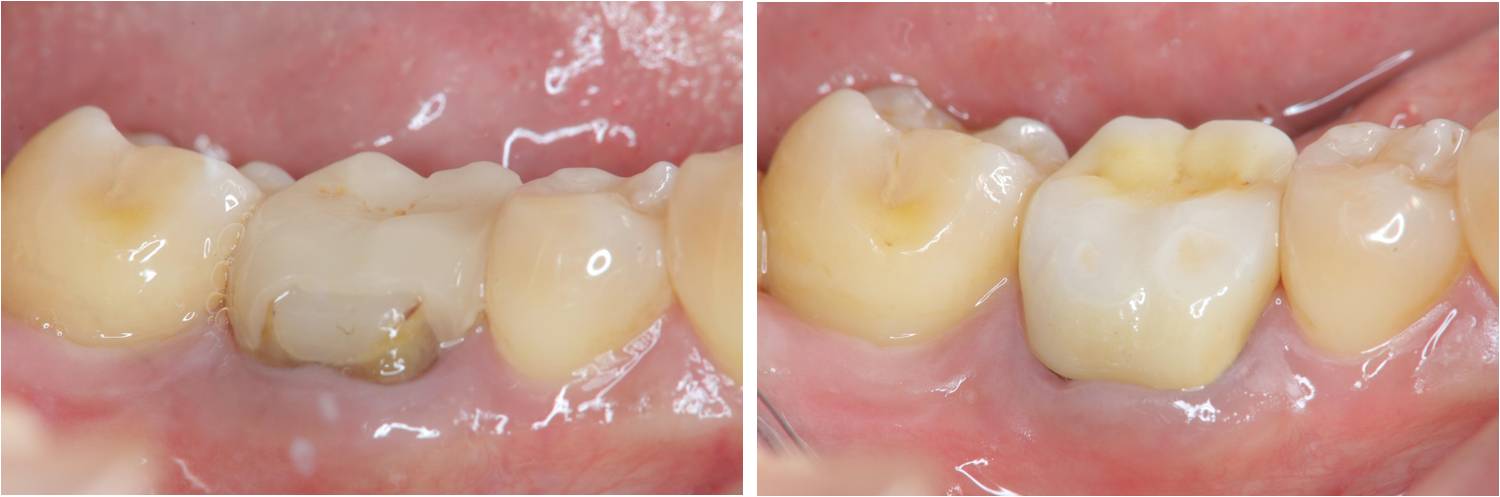

治療後,口內適應良好

牙齒邊緣密合度良好

術前、術後比較